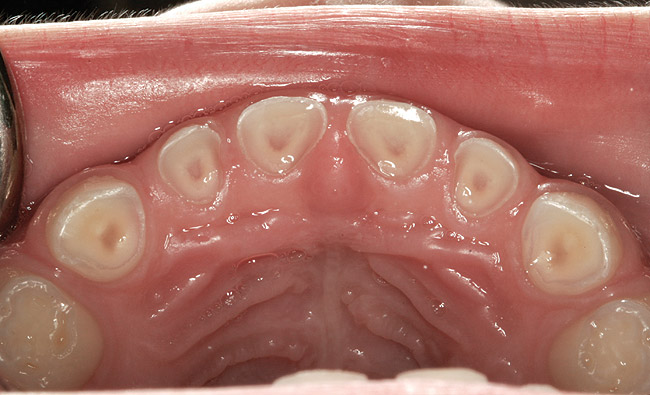

(3.) Three-year-old with a history of snoring, bruxing, and thumbsucking. Her father and brother were both diagnosed with OSA.

Figure 3

(4.) Patient presents bilateral crossbite and significant attrition. Father assists in retraction.

Figure 4